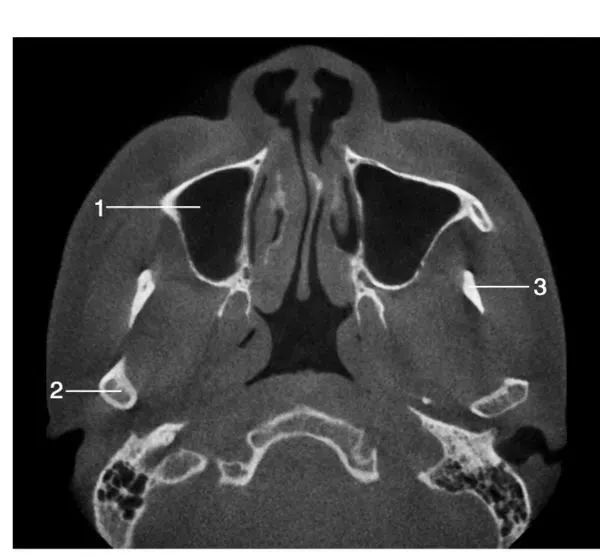

经下颌升支中份层面水平位图像

1.右侧上颌窦; 2.右侧髁突 ; 3.左侧喙突